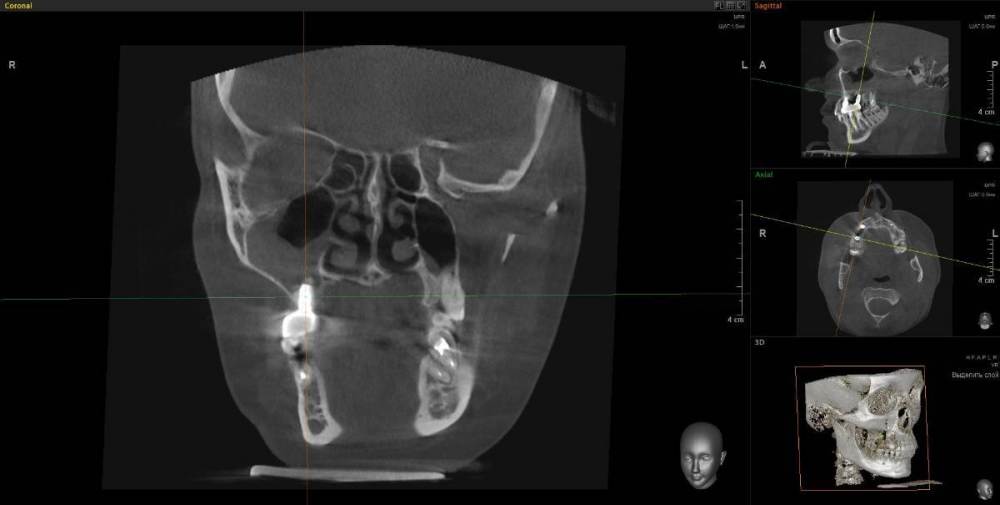

1. Из-за сильного воспаления верхнего зуба костная кость растворилась и дошло до пазух носа. Зуб рекомендуют удалить

2. Импланты установила 2 года назад, в итоге заплачено было 200 тыс. с учетом циркониевых коронок. На КТ обнаружилось сильное воспаление, как следствие растворилась костная ткань импланты, доктор сказал уже не спасти.

IMHO. Зуб 18 стоит удалить, зуб 17 стоит полечить. Имплантат в позиции 16, похоже, придётся удалить, имплантат в позиции 14, на мой взгляд, вне опасности.